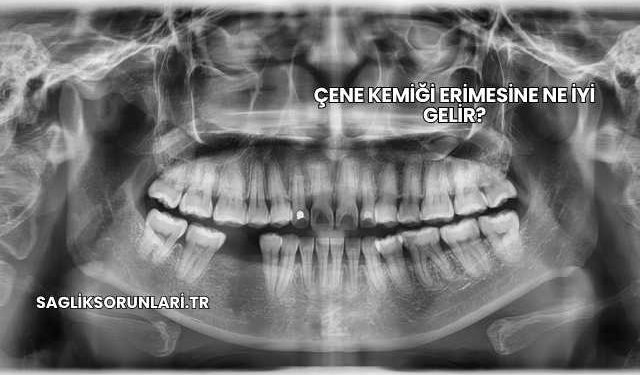

Çene Kemiği Erimesi Nedir?

Çene kemiği erimesi, diş kaybı, periodontal hastalıklar ya da travmalar sonucu çene kemiğinde meydana gelen hacim kaybıdır. Bu durum zamanla kemik yoğunluğunun azalmasına yol açarak implant uygulamasını zorlaştırır ya da imkansız hale getirebilir.